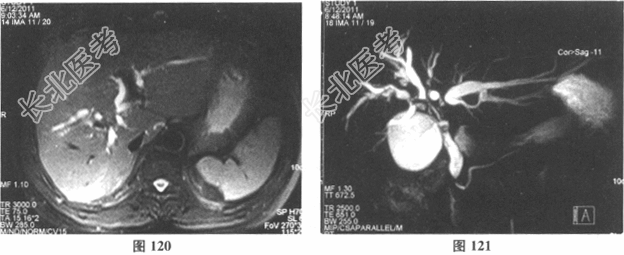

- [材料题] 患者男性,57岁,主诉"反复发热、右上腹痛2个月,巩膜皮肤黄染1周"入院。患者于2个月前无明显诱因突然出现发热、右上腹胀痛,当地医院就诊,给予抗炎对症治疗后缓解。之后发热、右上腹胀痛反复发作,外院行腹部CT检查示:"高位胆道梗阻,伴肝内胆管扩张"。1周前患者出现巩膜皮肤黄染。病来体重无明显变化,大便灰白,小便颜色加深。否认肝炎、结核病史。入院查CA19-9 1890U/ml,CEA2.56U/ml,AFP2.3ng/ml,CA12513.3U/ml,MRI和CT结果见图120~图125。

- 多项选择题1.该患者的临床诊断考虑为( )

- 多项选择题2.该患者的Bismuth-Corlette分型为( )

- 多项选择题3.该患者按"国际胆管癌协会分期系统"的分型是( )

- 多项选择题5.[提示] 该患者入院后化验结果:Hb103g/L, WBC7.47×109/L,N0.622, PLT332×109/L;PT12.9s, APTT35.1s,PTA99%, INR1.0,Fib6.72g/L; ALT74.2U/L,AST103.3U/L, Alb31.7g/L,TB114.3μmol/L, DB81.2μmol/L,ALP964.4U/L, GGT667.8U/L;乙肝、丙肝、HIV、梅毒检查均阴性。患者身高170cm, 体重69kg,标准肝体积=1302ml; 根据CT和MRI计算肝脏右半肝体积=810ml;左半肝体积=492ml。该患者的手术方式应选择( )